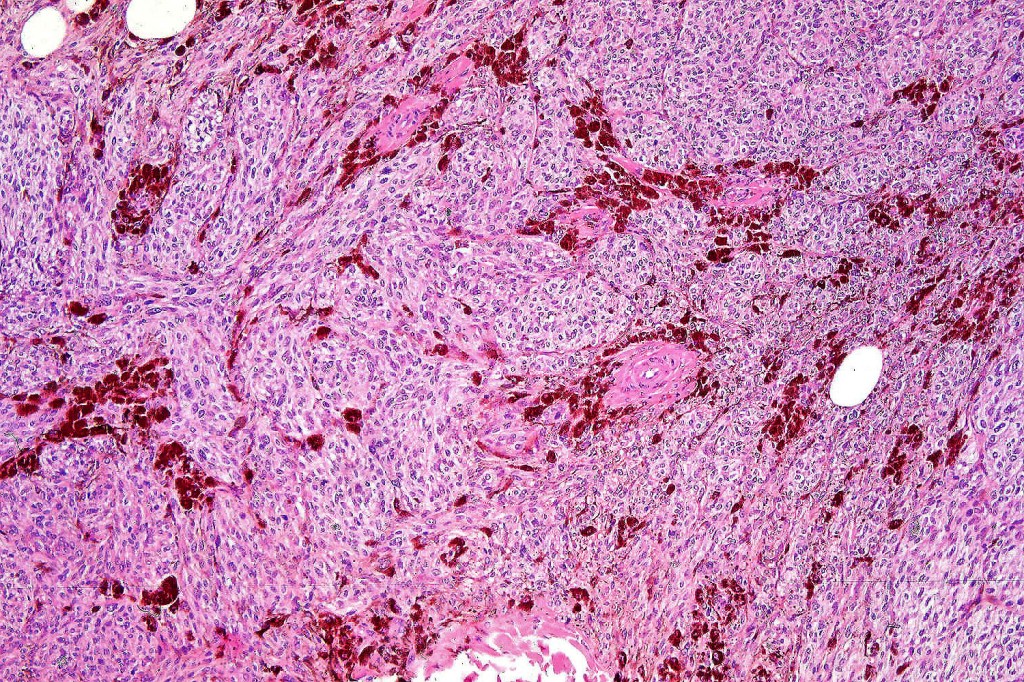

Histological features

•Most characteristic is the dumbbell silhouette although a plague morphology may also be encountered

•Admixture of spindle cells, pigmented bipolar or dendritic cells & melanophages

•An alveolar pattern is characteristic particularly with clear cell nodules

•Stromal fibrosis, myxoid change, vascular hyalinization with cyst formation are often seen